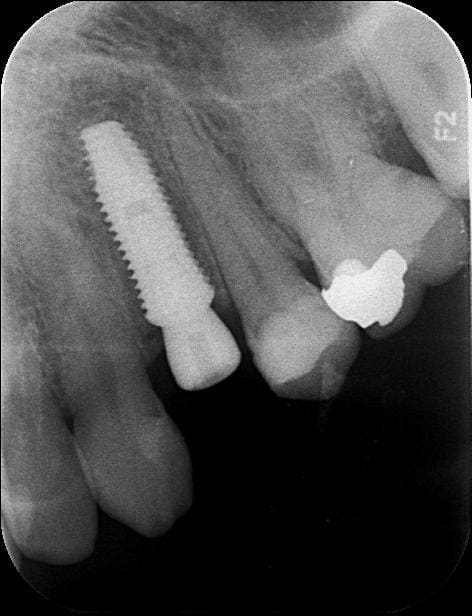

Rorschachwhite tx6rqr - Eugenol

Tiens Pluton, un 4.5 par 12, j'aurais du poser un 4 je me serais fait moins peur :-)

Mais ce n'est pas pour l'axe que je le poste, juste regarde le niveau osseux à trois mois d'écart, le pilier de cicat a été vissé le jour de la pose le 17/09 !

AMHA c'est LE + de cet implant : la stabilité osseuse.

J'ai les mêmes RX pour tout ceux que j'ai posé depuis le début de l'année.

CC.

Photo pluton1b h9n4ea - Eugenol

quoi ton axe...il est bien placé ton implant....bon pour pinailler, un chouilla plus mésial pour être parfait

j'avais un peu peur de mêler expansion et cet implant...mais non, comme sur des roulettes...

faut dire qu'on est aussi aidé par des forets particulièrement sécants...et donc on peut les faire tourner à très faible vitesse...juste pour finir d'aménager le logement implantaire...

et comme il n'est pas trop conique...moins de risques finalement de péter la corticale à l'insertion de l'implant...insertion par ailleurs particulièrement "douce" et progressive...le double filetage carré pas trop agressif n'y est certainement pas étranger...

et le blocage terminal est "franc"...bref...pour le moment très content...;-)